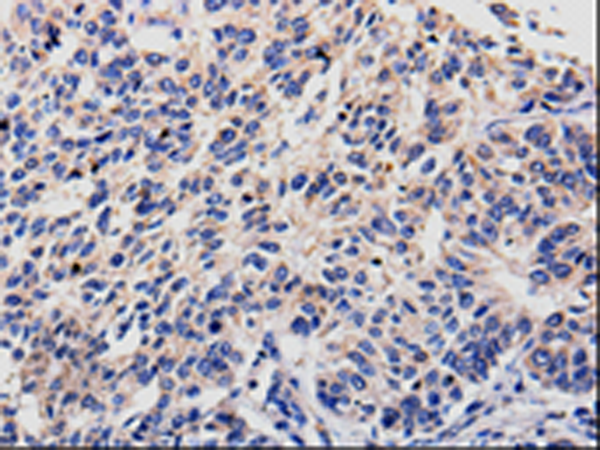

分类: 科研抗体货号: P10646别名: C10orf22应用: WB,IHC反应种属: Human, Mouse